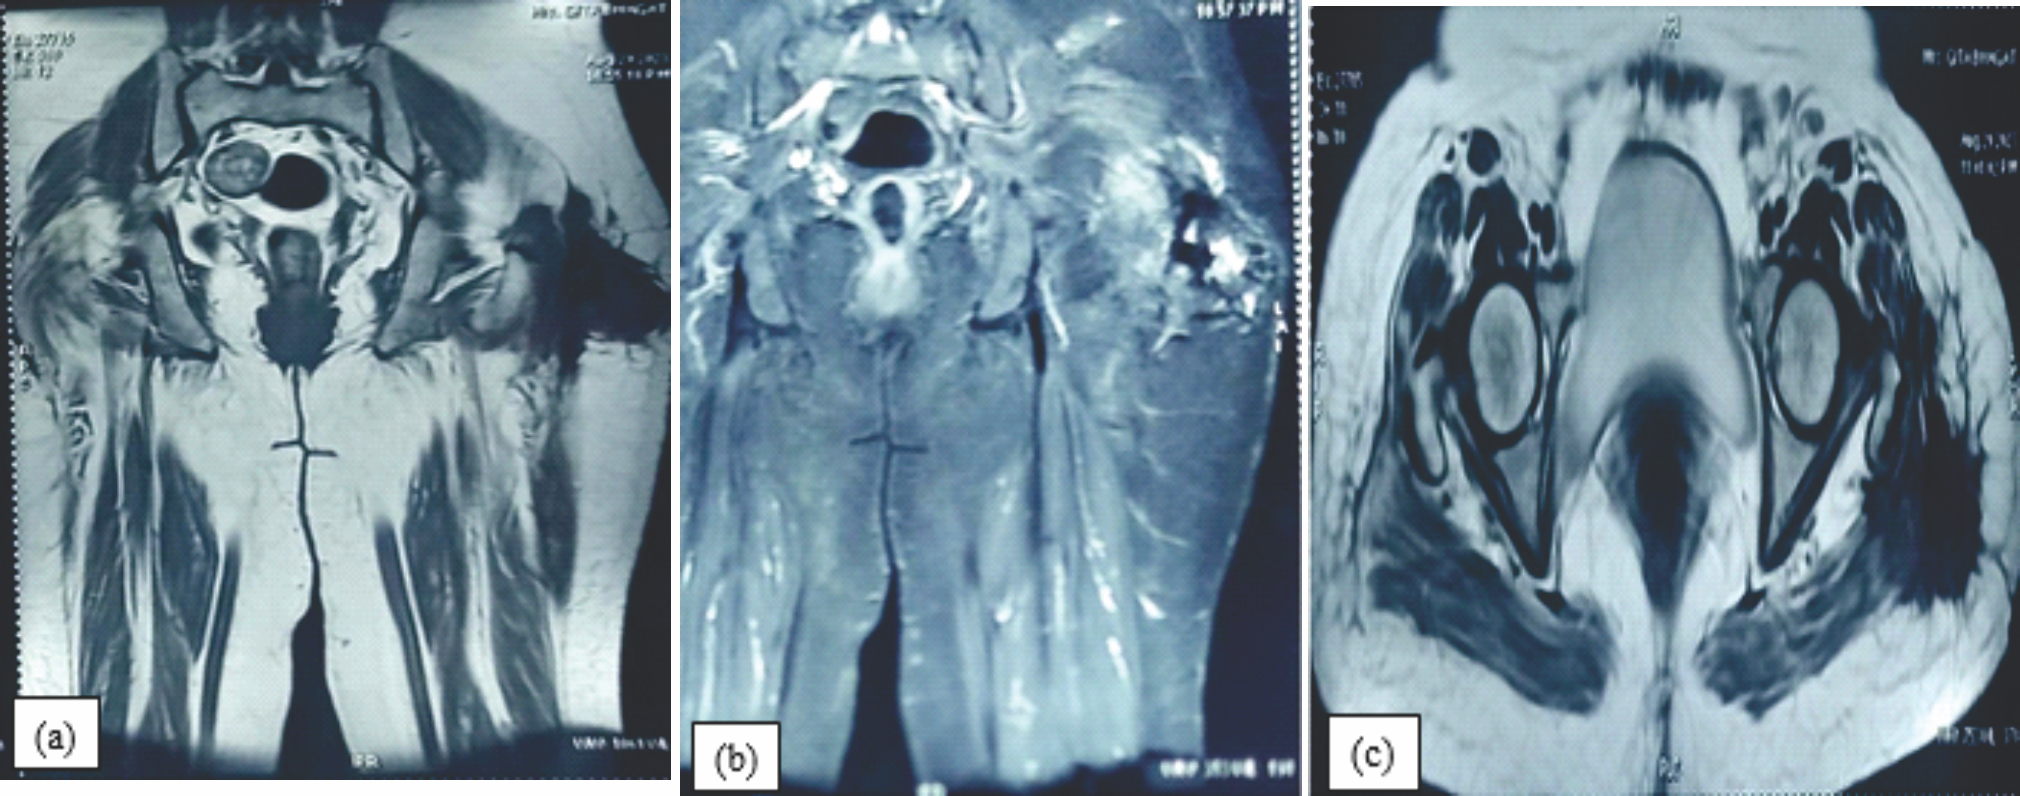

Figure 3: (a, b &c): Coronal T1, STIR & axial T2, images of the hip reveal a periarticular , multilobulated mass with mild internal T2 hyperintensity .The mass is well demarcated, lobulated and predominantly low signal on T2 weighted sequences suggestive of calcification noted in the left side.

On post-contrast images, mild enhancement was seen in the non-calcified soft tissue, and there was no involvement of the bony structure. Magnetic resonance imaging (MRI) revealed a subcutaneous lobulated mass over the left greater trochanteric region of the femur, posterolaterally with fixity to the underlying deep fascia and gluteus maximus. Overlying skin showed focal thickening and scar formation (Fig. 3a, b, c).